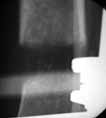

S/P Nailing

AP

lateral

ST healed